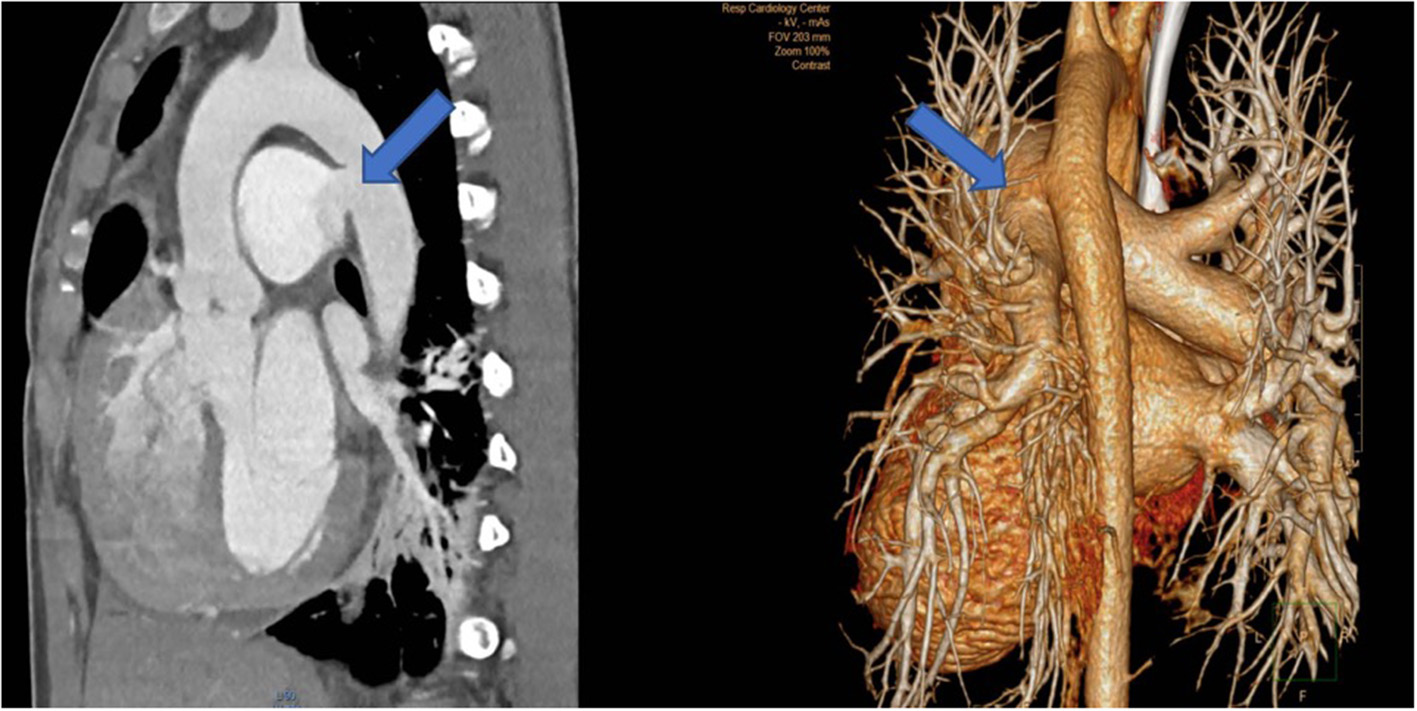

The second case was a 28-year old female who was operated at the age of 10 years and received a patch enlargement as a treatment of aortic coarctation. She did well until the age of 27 when a large pseudo-aneurysm was suspected incidentally on a chest x-ray performed for pulmonary reasons and confirmed by CT-scan. This picture showed in a certain way the challenges of planning surgery with rather simple imaging possibilities in emerging countries. Re-operation was indicated and performed through a lateral thoracotomy under femoro-left atrial bypass and moderate hypothermia (28°C) since a safe clamping of the proximal descending aorta was expected to be difficult. In fact, the aneurysm originated from the suture line of the patch with the native aorta and covered the whole proximal third of the descending aorta. Once the targeted core temperature was reached, the bypass was stopped and the aneurysm opened. Since the period of circulatory arrest was not expected to be prolonged, no additional cerebral protection was planned. Replacement of the proximal descending aorta was performed with the proximal suture line at the level of the left subclavian artery in the open arch technique (circulatory arrest time 14 min) and the distal one at the mid-level of the descending aorta. The vascular graft was approximately 10 cm in length. Weaning from cardiopulmonary bypass was difficult because of a coagulopathy and severe oozing though the graft but inclusion using a pericardial patch allowed the situation to be controlled. The patient was extubated on postoperative day 2. Unfortunately, she had severe pulmonary problems a week later and had to be re-intubated, but unfortunately died 10 days after surgery from respiratory failure.

The second patient is a 45-year old female known for a Takayasu arteriitis who suffered from drug-resistant arterial hypertension, renal failure and symptoms of claudication Fontaine stage IIb-III with a walking distance of <100 m and sometimes pains at rest. She presented with a localized severe calcific stenosis of the descending aorta with a resting lumen of 3–4 mm at the narrowest site (Figure 13 both right). She was originally referred for evaluation of an endovascular approach but the interventional radiologist denied this possibility. Finally, she received an extra-anatomic ascending-to-infrarenal aortic bypass. A 16 mm vascular graft was anastomosed on the beating heart at the right lateral level of the tangentially clamped ascending aorta. The graft was then brought to the right close to the right atrium and passed through the diaphragm, then through the bursa omentalis to the retroperitoneum and the infrarenal aorta where the distal anastomosis was constructed approximatively 4–5 cm above the aorto-iliac bifurcation. Postoperative course was uneventful and symptoms as well as the arterial hypertension greatly improved soon after surgery. CT-scan demonstrated the correct position of the extra-anatomic graft (Figure 14).

Figure 14

Postoperative 3-D reconstruction of the CT-angio following ascending to infrarenal bypass in the patient with very calcified and narrowed descending aorta following Takayasu disease.